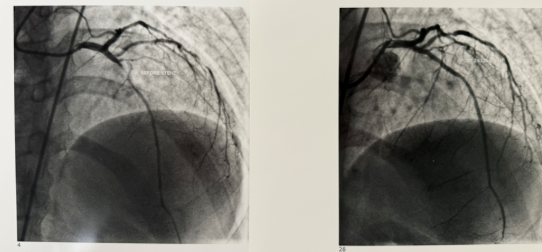

Stent placement after balloon angioplasty widens a narrowed coronary artery.

- During the procedure, a small balloon attached to a thin catheter is guided to the site of the blockage. The balloon is gently inflated to widen the artery and restore blood flow. In most cases, a small flexible wire mesh tube called a stent is placed inside the artery to help keep it open permanently.

- PCI improves blood flow to the heart muscle, relieves chest pain (angina), and may reduce heart damage during or after a heart attack. It is often performed immediately following a diagnostic cardiac catheterization when a significant blockage is found.